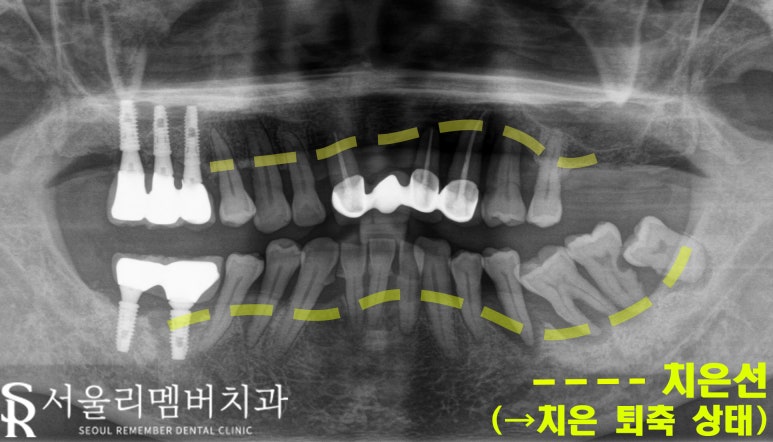

진단: 치아 흔들림과 잇몸 문제

엑스레이와 구강 사진을 통해 확인한 결과,

주소대로 이가 흔들리고 있었습니다.

잇몸 상태도 좋지 않았으며,

치은 퇴축이 진행되어 뿌리가

많이 드러난 모습이였죠.

이런 경우, 단순한 잇몸 치료와 크라운으로는

해결이 불가능하고 전체적으로

implant를 식립하는 방법을 고려해야 됐습니다.